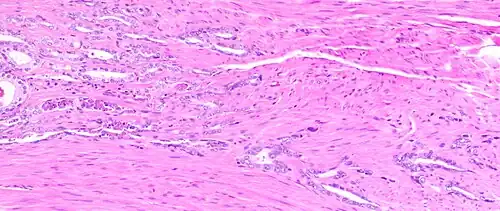

Micrograph showing inflamed prostate (H&E stain) with large amount of darker cells (leukocytes); area without inflammation seen on the left

Prostatitis is inflammation of the prostate gland. It can be caused by infection with bacteria, or other noninfective causes. Inflammation of the prostate can cause painful urination or ejaculation, groin pain, difficulty passing urine, or constitutional symptoms such as fever or tiredness.[28] When inflamed, the prostate becomes enlarged and is tender when touched during digital rectal examination. The bacteria responsible for the infection may be detected by a urine culture.[28]

Acute prostatitis and chronic bacterial prostatitis are treated with antibiotics.[28] Chronic non-bacterial prostatitis, or male chronic pelvic pain syndrome is treated by a large variety of modalities including the medications alpha blockers, non-steroidal anti-inflammatories and amitriptyline,[28] antihistamines, and other anxiolytics.[29] Other treatments that are not medications may include physical therapy,[30] psychotherapy, nerve modulators, and surgery. More recently, a combination of trigger point and psychological therapy has proved effective for category III prostatitis as well.[29]